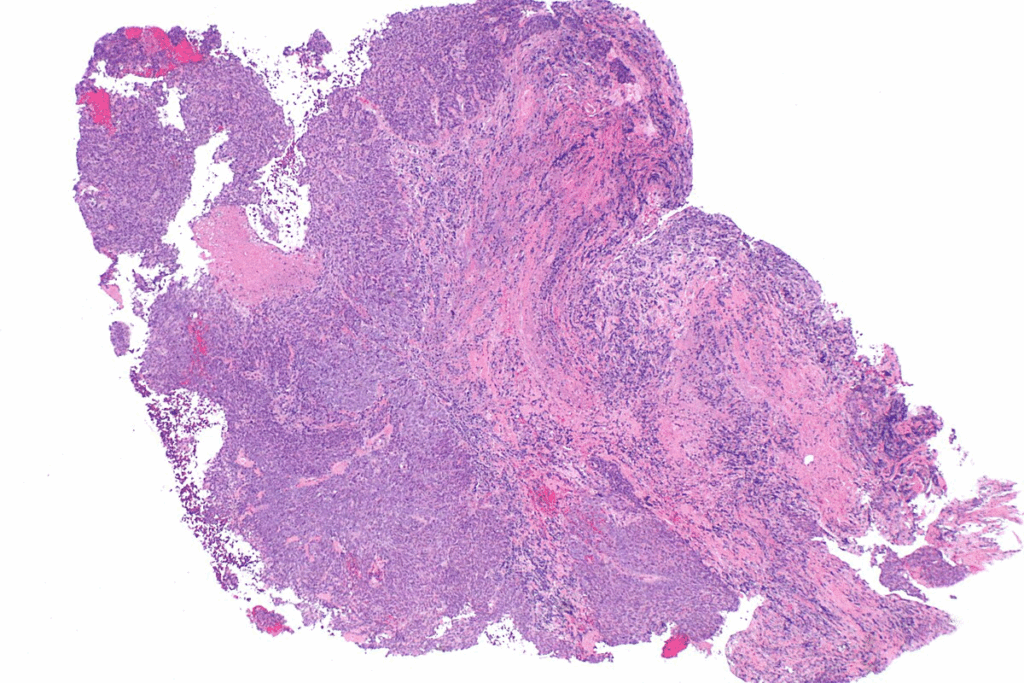

Biopsy and Pathological Confirmation

The final step is a biopsy and pathological exam. A biopsy takes a tumor sample for microscopic examination. This confirms neuroblastoma and helps understand its nature.

Accurate diagnosis is the cornerstone of effective treatment planning. By combining screening, imaging, lab tests, and biopsy results, doctors can fully understand the disease. This allows them to create a treatment plan that meets the child’s specific needs.